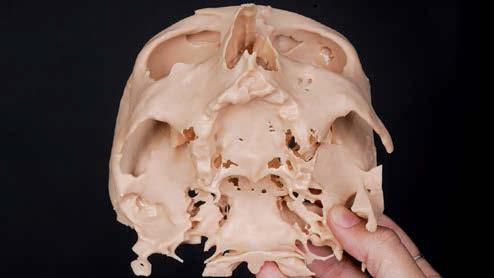

Elevación de seno transcrestal con implantes cortos versus elevación de seno convencional con ventana lateral

Estudio retrospectivo comparativo a boca partida

La rehabilitación del maxilar superior posterior mediante implantes dentales se ha visto condicionada clásicamente por la neumatización excesiva del seno maxilar al perderse los dientes relacionados con el mismo (dientes antrales) (1, 2). En estos casos, se pierde gran parte de la altura del reborde óseo residual generándose atrofias verticales, que pueden limitar, de forma importante, la inserción de implantes de manera directa (3-5).

Esta ocupación del seno de la cresta residual adyacente es diferente en función del diente a extraer, la pérdida ósea asociada a ese diente y la presencia, o no, de comunicación de la potencial infección odontógena con el seno. Aun así, es frecuente que la mayor pérdida en altura derivada del proceso de neumatización del

seno post-extracción sea para el segundo molar o cuando se realiza la extracción del primer y segundo molar simultáneamente (6). Cuando los dientes se han perdido y el seno ha ocupado gran parte del volumen óseo residual de la zona del maxilar superior en su zona posterior, clásicamente, se realizaba una técnica de elevación de seno por abordaje lateral para, mediante un injerto óseo compuesto por diferentes materiales (hueso autólogo, biomaterial o mezcla de ambos generalmente), volver a recuperar la altura de cresta ausente y poder insertar los implantes dentales posteriormente o en el mismo procedimiento, siempre que existiese un volumen óseo residual que permitiese que los implantes quedaran estables (7-9).

Ya que ambas técnicas quirúrgicas siguen hoy en día en pleno auge, aunque las indicaciones para cada una de ellas han evolucionado en el tiempo, quedando la elevación convencional únicamente indicada hoy en día en aquellos casos de 1-2 mm de volumen óseo residual (donde es muy complejo estabilizar un implante corto por elevación transcrestal), creemos útil poder comparar la evolución de ambos procedimientos en el tiempo, a ser posible en un mismo paciente, donde el resto de variables que puedan afectar al seguimiento sean iguales, y, por lo tanto, la comparación sea más útil. Por ello, hemos realizado un análisis retrospectivo de pacientes en los que se han realizado los dos procedimientos, uno en cada cuadrante superior y ver la evolución en el tiempo de los implantes insertados en cada caso. Con esta idea en mente, hemos llevado a cabo un estudio retrospectivo que evaluase estos factores, y que se detallan a continuación.

MATERIAL Y MÉTODO

Fueron reclutados de forma retrospectiva pacientes en los que se hubiesen realizado ambas

técnicas de abordaje de seno maxilar: elevación convencional o la inserción de implantes cortos y extra-cortos mediante elevación transcrestal, desde enero de 2010 en adelante. Todos los pacientes fueron estudiados antes de la inserción de los implantes mediante modelos diagnósticos, exploración intraoral y realización de un TAC dental (Conebeam) analizado posteriormente mediante un software específico (BTI-Scan II).